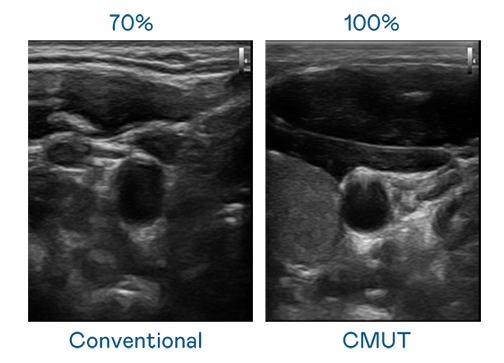

CMUT 技术是一种用电容式微机电元件来产生超音波讯号的技术。与传统 PZT 压电式技术相比,CMUT 频宽增加 30%,更宽频的超音波讯号让影像解析度大幅提升,是实现高影像品质医疗超音波扫描、促进精准医疗发展的关键技术。

大频宽带来超清晰影像

超音波影像的解析度高低,首先取决于探头能发出的讯号频宽。英国正版365 CMUT 可提供高清晰的超音波讯号,提供高频宽、高灵敏度、影像纹理细节更高的超音波影像,协助医护人员缩短影像判读时间及利用精准的医疗影像进行诊断。